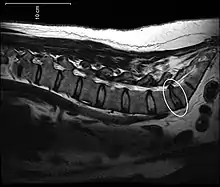

A disc protrusion is a medical condition that can occur in some vertebrates, including humans, in which the outermost layers of the anulus fibrosus of the intervertebral discs of the spine are intact but bulge when one or more of the discs are under pressure.

Many disk abnormalities seen on MRI that are loosely referred to as "herniation" are actually just incidental findings. These may be unrelated to any symptoms and are just bulges of the anulus fibrosus. Jensen and colleagues, in an MRI study of the lumbar spine in 98 asymptomatic adults, found that in more than half, there was a symmetrical extension of a disc (or discs) beyond the margins of the interspace (bulging). In 27 percent, there was a focal or asymmetrical extension of the disc beyond the margin of the interspace (protrusion), and in only 1 percent was there more extreme extension of the disc (extrusion or sequestration). These findings emphasize the importance of using precise terms in describing the imaging abnormalities and evaluating them strictly in the context of the patient's symptoms.[1]

A disc protrusion may progress to a spinal disc herniation, a condition in which there is a tear in the anulus fibrosus.